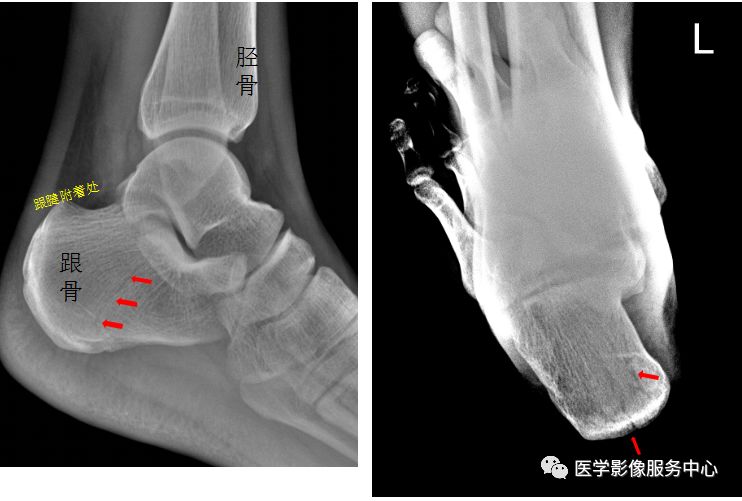

左侧跟骨见骨折透亮线,后缘骨皮质连续中断。左侧跟骨骨折。

右足斜位示 右侧跟骨前部见骨折透亮线。右跟骨前部骨折。